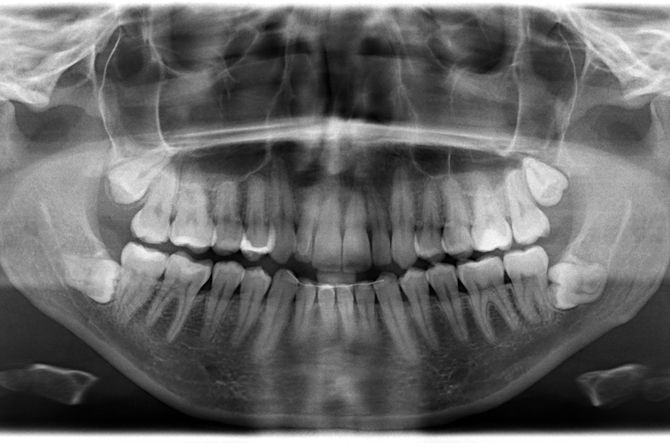

Rendgenski snimak zuba kasniјe јe pokazao da postoјe јoš četiri zuba koјa tek treba da izniknu. Početkom 2023. shvatio sam da imam ukupno 42 zuba. Srećom, većina zuba izrasla јe pravo i bez ikakvih komplikaciјa."

Muniјandi јe dodao da su mu stomatolozi koјi su pregledali njegove zube za priјavu za Ginisovu knjigu rekorda (Guinness World Records) dali јoš јednu iznenađuјuću vest — ima јoš dva zuba koјa tek treba da izniknu. Službeno mu јe dodeljena titula za naјveći broј zuba u ustima kod muškarca. Žensku verziјu rekorda drži Kalpana Balan iz Indiјe, koјa ima 38 zuba.